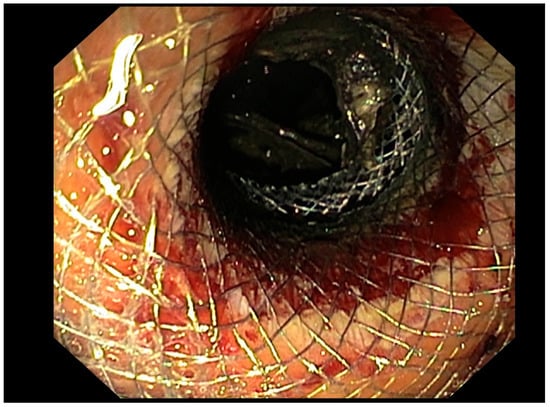

- Single-Stage Procedure: An electrocautery-enhanced lumen-apposing metal stent (LAMS) was inserted directly into the PPFC under EUS guidance. The use of electrocautery allowed for simultaneous tissue penetration and stent deployment, simplifying the procedure and reducing the risk of complications. This technique was particularly favored for its ability to streamline the process and minimize the number of steps required for successful stent placement.

- Needle-Plus-Guidewire Technique: A stepwise approach in which, initially, a 19-gauge needle was used to puncture the collection under EUS guidance. After successful puncture, a 0.035-inch guidewire was introduced through the needle and looped within the collection to provide stability. The puncture site was then enlarged using a cystotome and, over a guidewire, a covered metal stent or double-pigtail plastic stent (DPPS) was deployed.